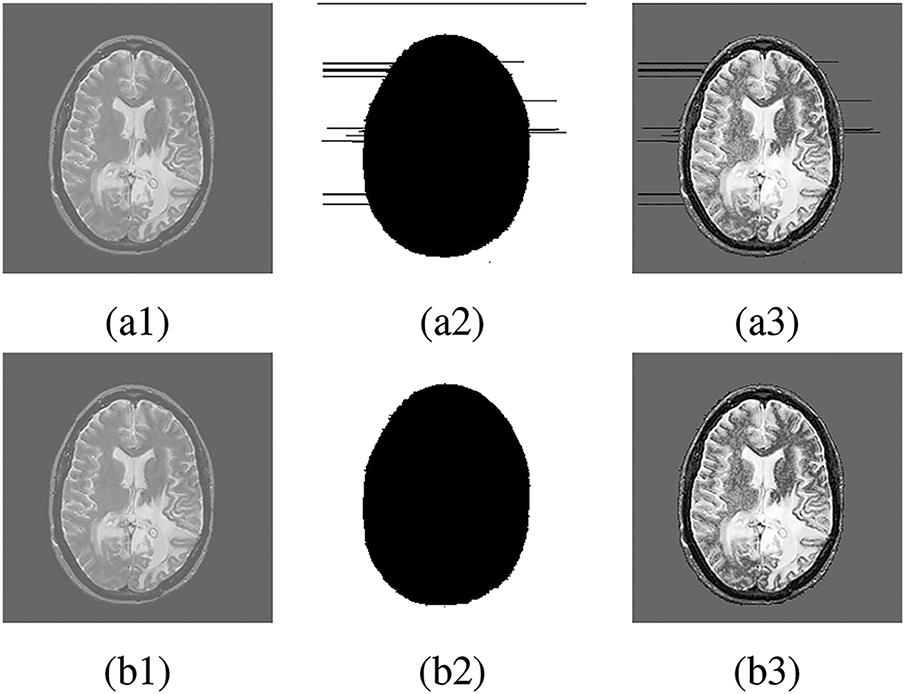

Figure 8: FR and NFR segmentation between existing works and proposed approach. (a1), (b1) Original medical image, (a2), (b2) Segmentation by [46], (a3), (b3) Segmentation by [49], (a4), (b4) Segmentation by [50], (a5), (b5) Segmentation by proposed method